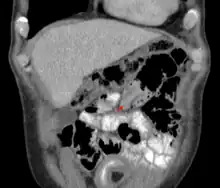

An intussusception as seen on CT

Small intestinal invagination on computed tomography